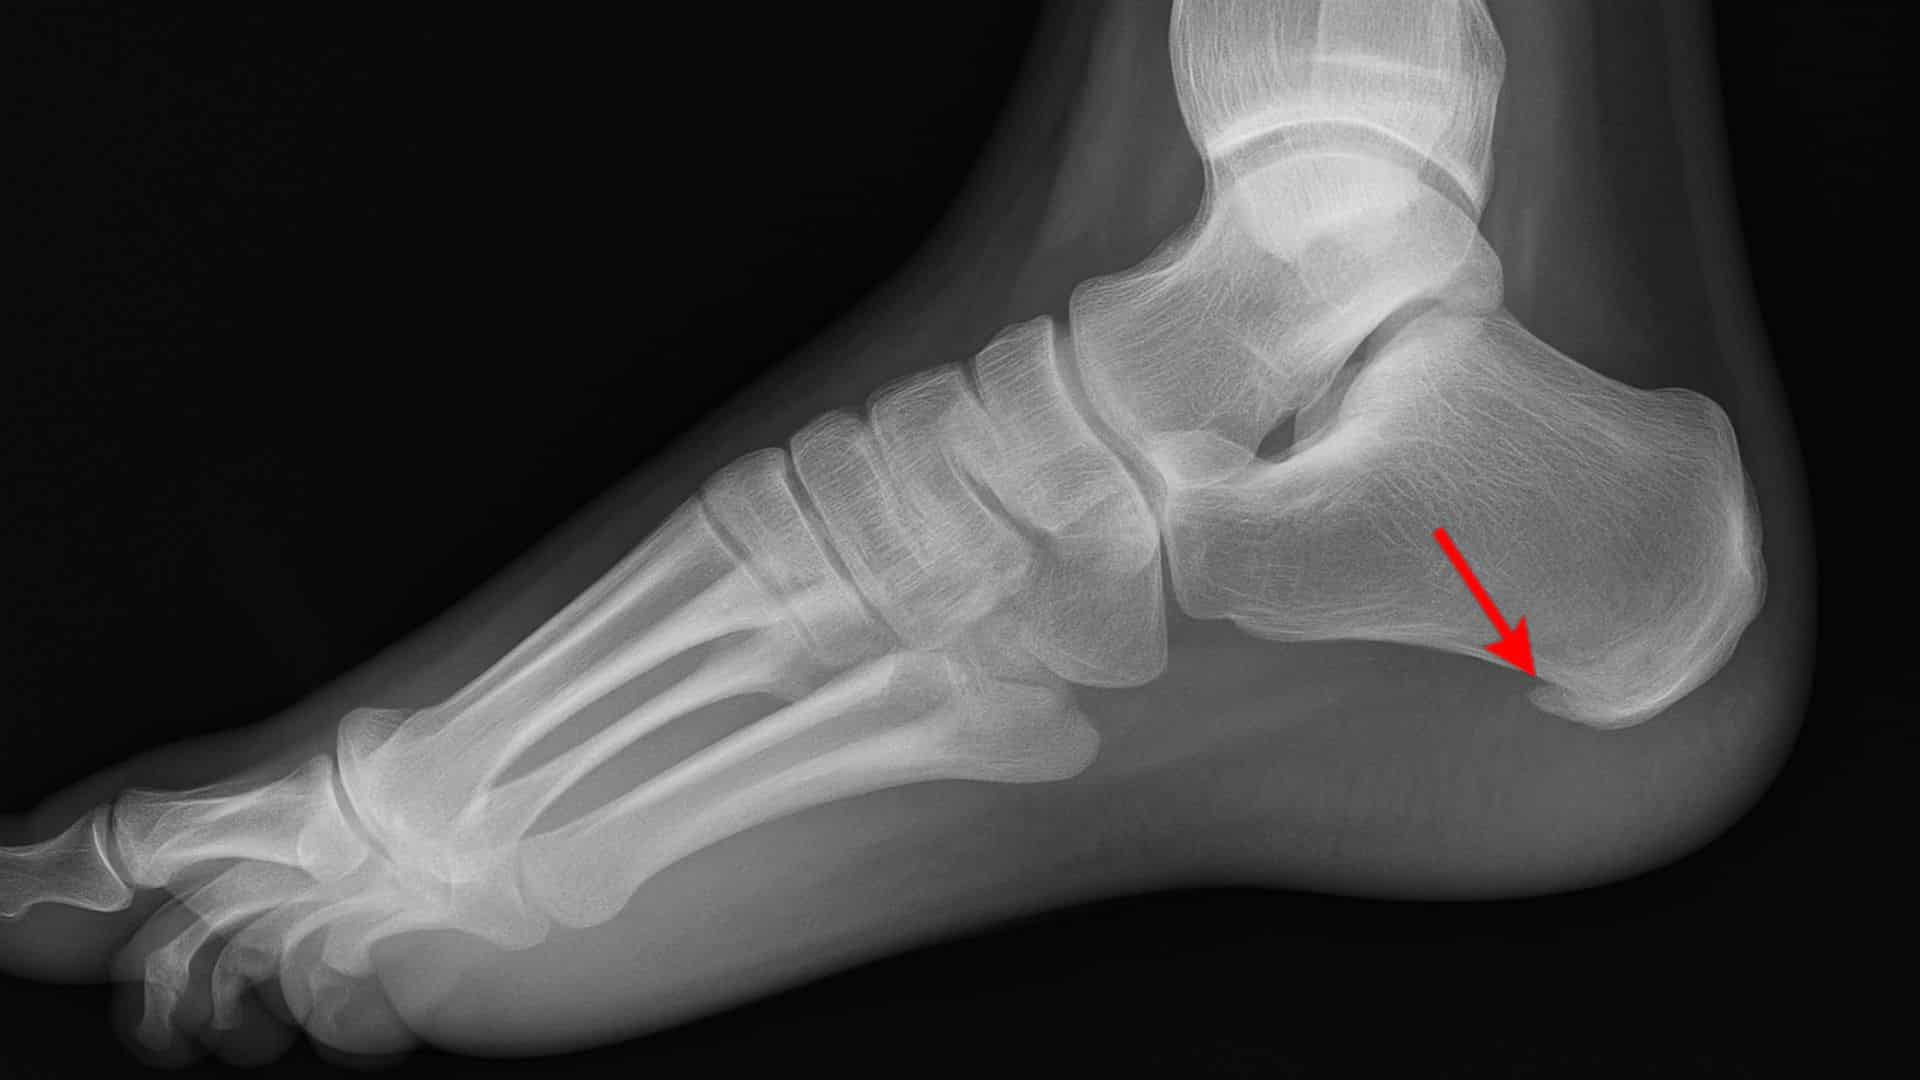

20. Bone Spurs

Bony projections form along bone edges, often due to arthritis. Nearly 60-80% of people over 50 develop bone spurs. They cause sharp, stabbing foot pain and difficulty walking.

Bone spurs can form anywhere in the foot but commonly affect the heel and toe joints. They may not cause pain until they rub against other bones or soft tissues.

Quick Fix: Wear shoes with Good Arch Support and maintain a Healthy Weight.